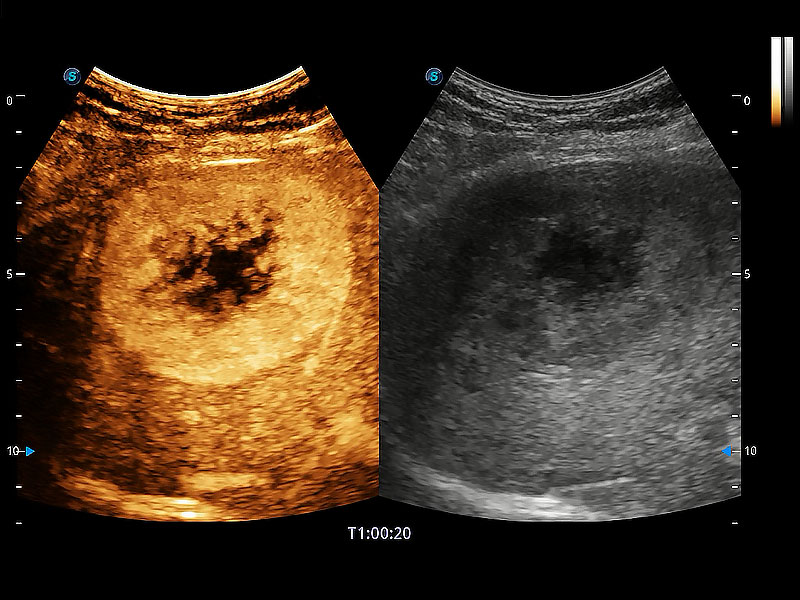

非線性融合造影成像充分利用諧波和基波信號,為難以觀察的血流進(jìn)行增強(qiáng)顯像。可用于線陣、凸陣、微凸陣、相控陣探頭。